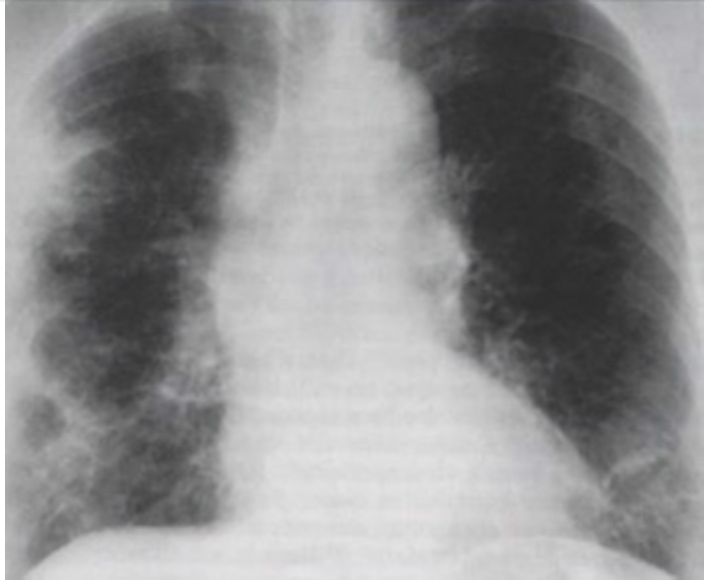

(SURCE 2015 ACESSO DIRETO) - Paciente feminina, 30 anos, com história de asma moderada e rinite alérgica persistente que se iniciaram há cerca de 10 anos. Relata piora da dispneia e da obstrução nasal nos últimos 6 meses e aparecimento de parestesia dolorosa em pé direito. A investigação mostrou espirometria com padrão obstrutivo acentuado com resposta significativa à prova broncodilatadora, tomografia dos seios da face com sinusite maxilar, hemograma com Hb: 11g/dl, Leucograma: 12.700/mm³ com 60% de neutrófilos, 26% de linfócitos, 13% de eosinófilos e 1% monócitos. Plaquetas: 190.000/mm³. A função renal, hepática e a dosagem sérica de IgE foram normais. Considerando o contexto clínico e a imagem da radiografia de tórax abaixo (VER IMAGEM), o diagnóstico mais provável é: A) Granulomatose de Wegener B) Síndrome de Churg-Strauss C) Pneumonite eosinofílica crônica D) Aspergilose Broncopulmonar Alérgica

Questão que aborda paciente com quadro de asma e rinite alérgica de longa data, mas que evoluíram com piora da dispneia e da obstrução nasal, há seis meses, além do surgimento de parestesia dolorosa em pé direito. Possui espirometria que corrobora diagnóstico de asma e tomografia de seios de face, que valida o diagnóstico de rinite. Exames laboratoriais demonstram leve anemia, leucocitose (12.700/mm³) com 60% de neutrófilos e 13% de eosinófilos, com plaquetas, função renal e hepática e dosagem sérica de IgE sem alterações. À radiografia de tórax, é possível observar a presença de infiltrados bilaterais difusos, com aparentes cavitações centrais. Diante do exposto, paciente que apresenta quadro de asma ou rinite, que evolui com eosinofilia periférica, acometimento orgânico (gastrointestinal, pulmonar, miocárdico, renal) por infiltração de eosinófilos, polineuropatia ou mononeuropatia múltipla, vasculite cutânea ou púrpura palpável, deve ser considerado portador de Síndrome de Churg-Strauss, ou granulomatose eosinofílica com poliangeíte. ALTERNATIVA B – CORRETA. De acordo com as demais assertivas: ALTERNATIVA A – INCORRETA: Embora o paciente com granulomatose de Wegener possa cursar com acometimento de seios paranasais, com destruição de septo nasal e palato, não é comum a existência de eosinofilia ou de asma. ALTERNATIVA C – INCORRETA: A pneumonite eosinofílica crônica só justificaria o achado pulmonar e a eosinofilia, não correspondendo ao restante do caso. ALTERNATIVA D – INCORRETA: A aspergilose broncopulmonar alérgica também só explicaria o acometimento pulmonar.